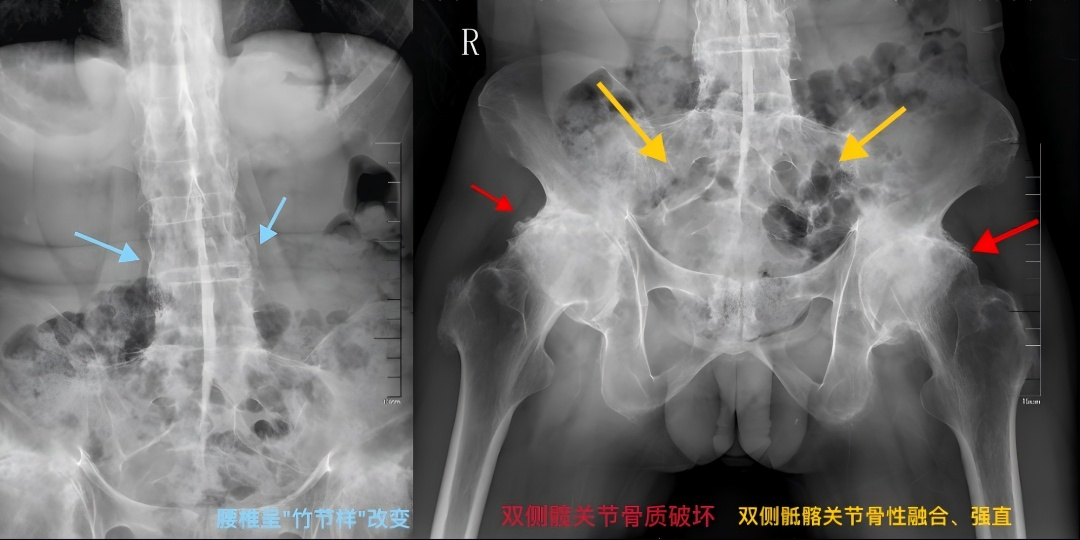

疾病通常从骶髂关节开始,逐渐向上蔓延至腰椎、胸椎乃至颈椎。若不及时控制,长期炎症会导致韧带骨化、脊柱融合,最终使脊柱如“竹节”般僵硬,丧失活动度,形成驼背等畸形。

强直患者的脊柱呈“竹节样”改变

随着病情发展,可能会导致脊柱、骶髂关节、髋关节等出现强直性的改变,严重者整个脊柱会像竹子般僵硬,甚至畸形、致残,并可伴有不同程度的心、肺、眼、肾等多器官损害。发病时,患者疼痛难耐,备受煎熬,并且该病会绵延一生,因此被称为“不死的癌症”。